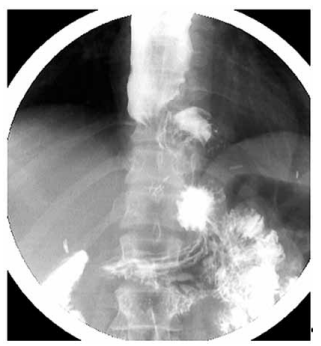

Realizou o esofagograma apresentado a seguir:

(Arquivo pessoal; imagem usada com autorização)

Considerando a história e os achados do exame, qual é a conduta mais adequada?